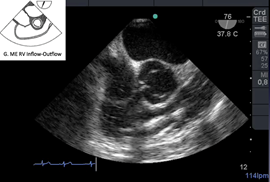

Otras veces la causa de PC perioperatorio es el tromboembolismo pulmonar. ETE tiene 80% de sensibilidad y 100% de especificidad para detectar embolia de pulmón. (Figura j)

Figura j: Imagen medioesofágica tracto de entrada y salida de VD.Trombo que migra del ventrículo derecho hacia la arteria pulmonar.